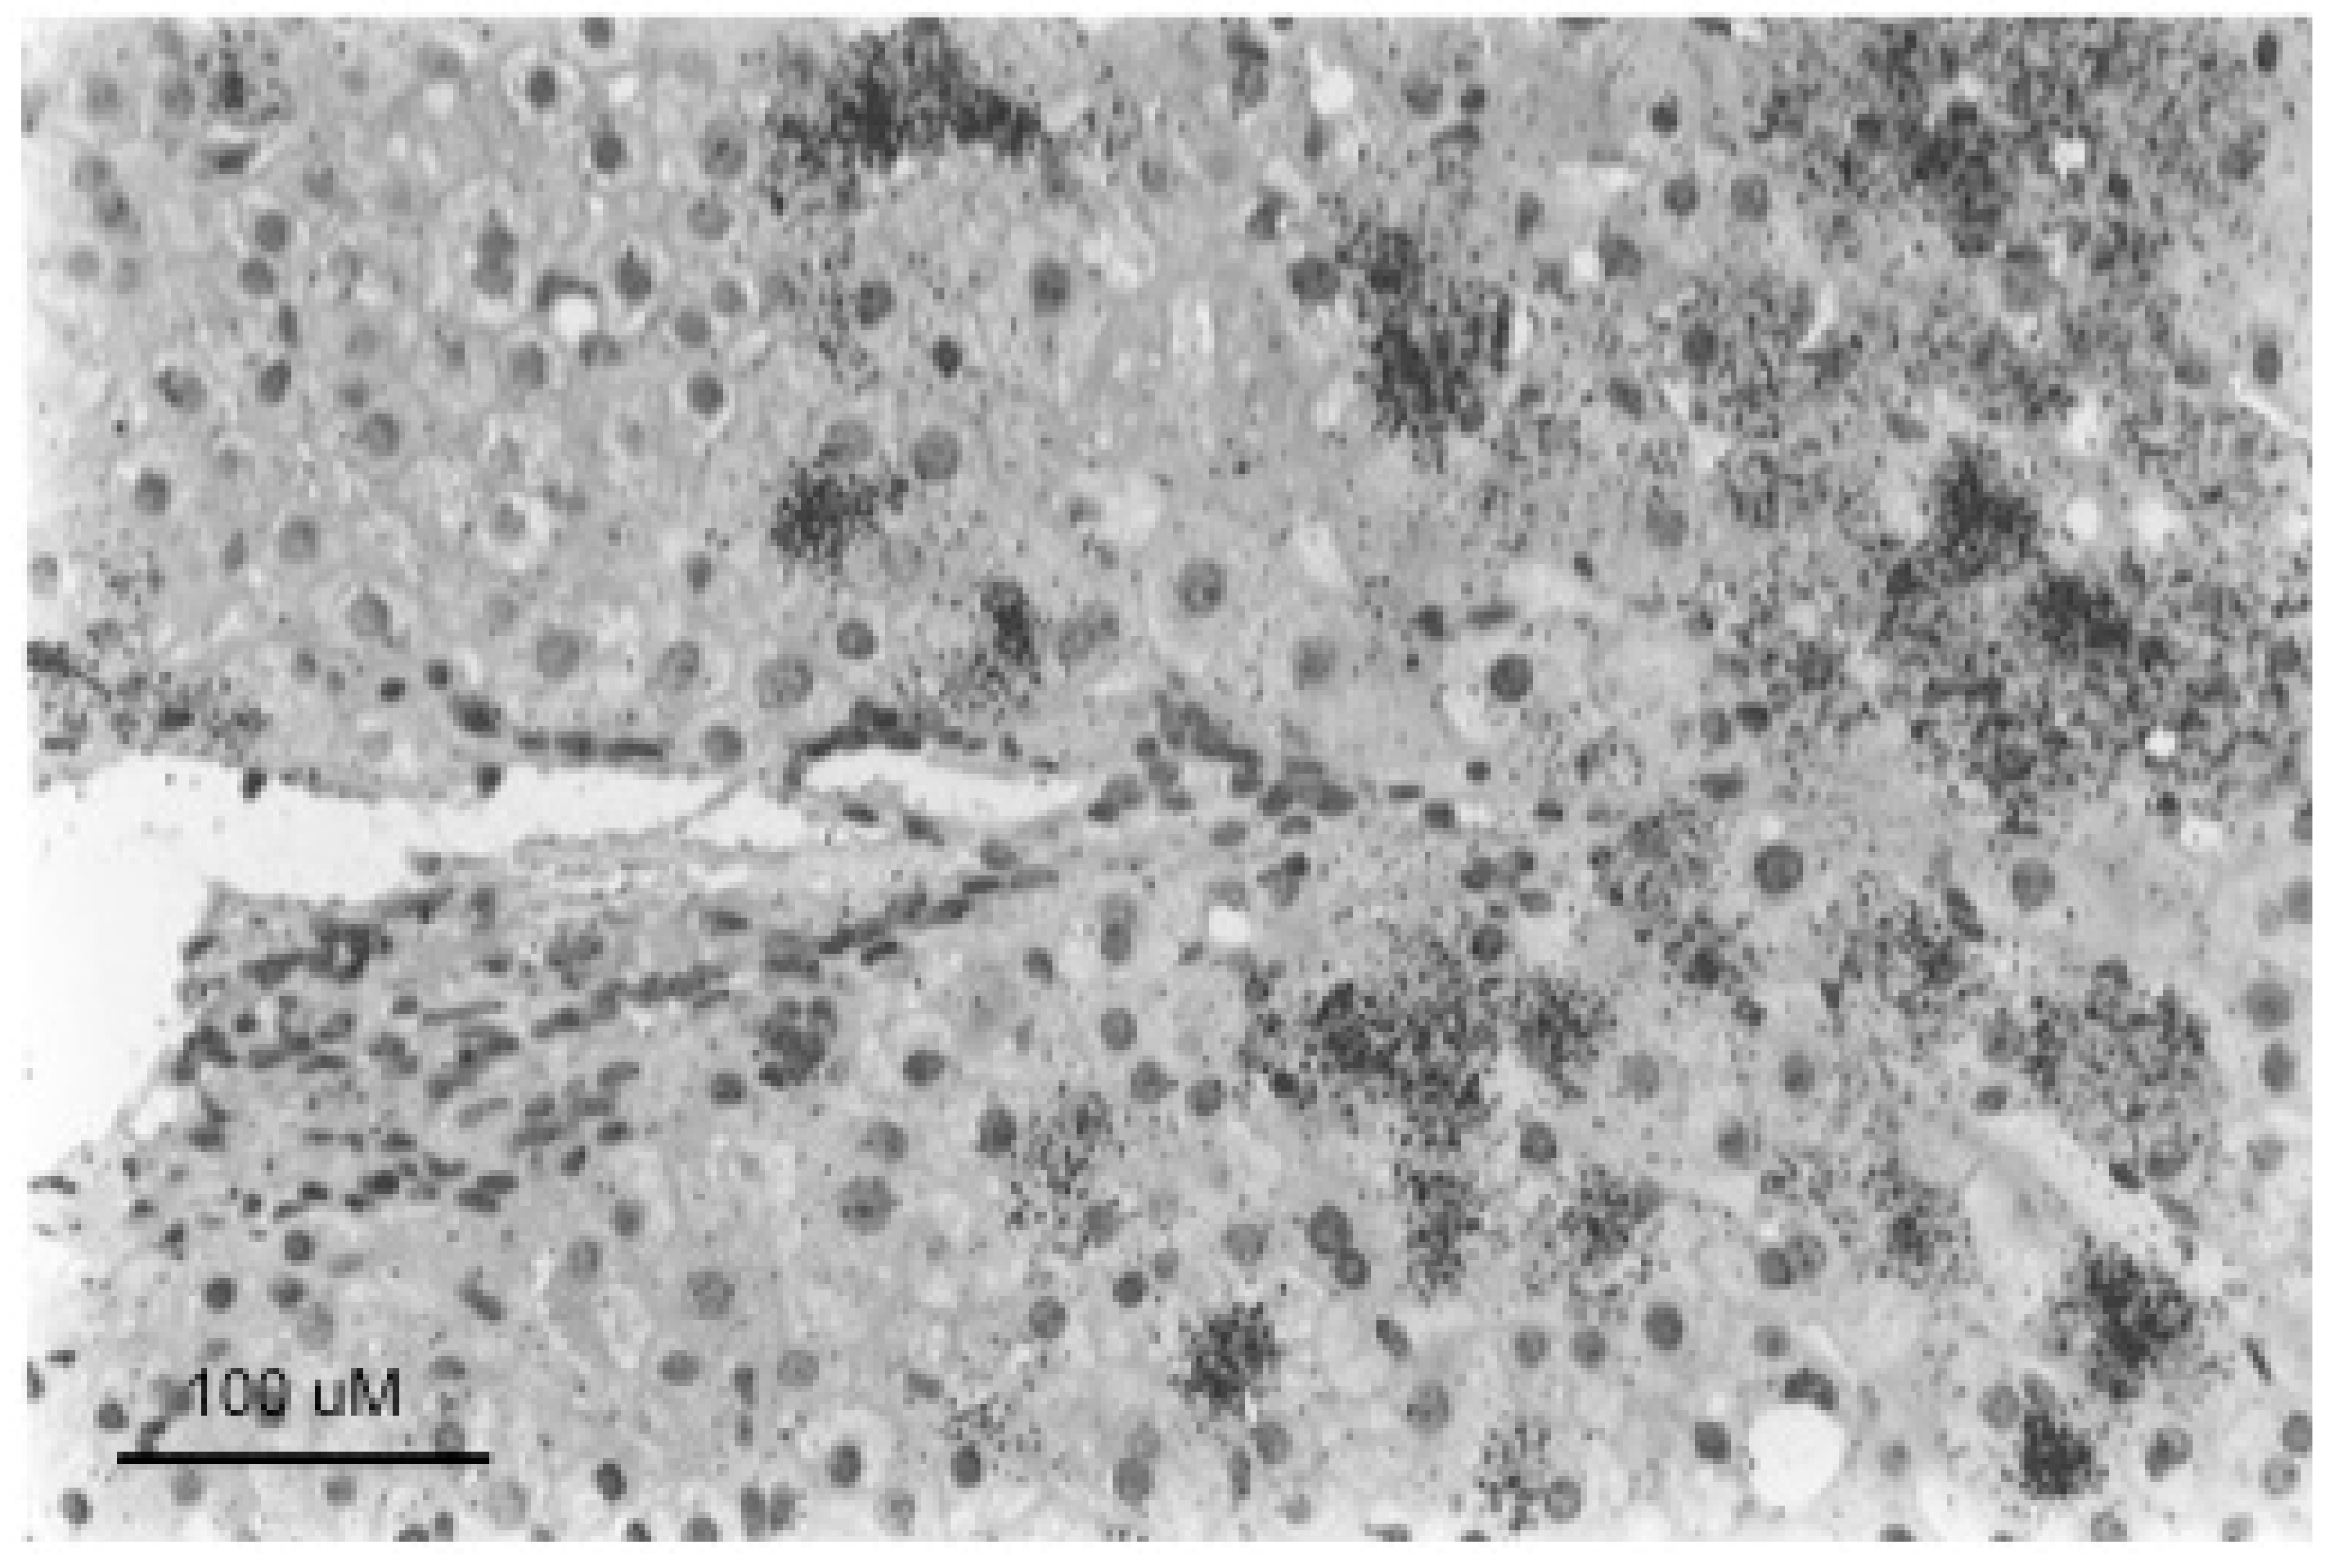

The change in the hepatocyte population to a less virus-productive state is consistent with the trend to a progressive drop in virus titers during the course of chronic HBV infection. Early in infection, the virus appears to infect the majority of hepatocytes, at least in chimpanzees, where early stages of HBV infection have been most thoroughly studied [86,87,88,89,90]. This is typically followed by a decline in the percentage of infected hepatocytes during the long course of chronic HBV infection. To a small extent this decline in infected hepatocytes is also observed in chronically WHV-infected woodchucks, which have a much shorter life span of about three years. Figure 4 (adapted from reference [91]) shows in the left-hand panels a focus of WHV core antigen-negative, but otherwise normal appearing hepatocytes, late in WHV infection of a woodchuck with high titer viremia. Thus, the cells are apparently resistant to WHV infection and/or expression. In addition, the appearance of these cells in a focus suggests that they represent a single hepatocyte clone. (It should be noted that foci of histologically altered hepatocytes (FAH) which are WHV-negative, and display elevated expression of N-myc [92], are common in the chronically WHV-infected woodchuck [92,93,94], as illustrated in Figure 4, right-hand panels).

Figure 4.

Foci of normal and basophilic, woodchuck hepatitis-virus (WHV) core antigen-negative hepatocytes in chronically WHV-infected woodchuck liver. The left-hand panels are consecutive sections of WHV-infected liver, either immune-peroxidase stained using antibodies to WHV core antigen (top) or Hematoxylin and Eosin (H&E) stained (bottom), showing a focus of histologically normal, WHV core antigen-negative hepatocytes. The right-hand panels are similar consecutive sections showing a basophilic focus of altered hepatocytes (FAH) that are also WHV core antigen-negative. Figure adapted and reproduced with permission from reference [91], Xu et al., Virology, published by Elsevier, 2007.

Well-defined foci of hepatocytes, negative for HBV replication, as assessed by HBcAg staining of tissue sections, have also been observed in chronically HBV-infected chimpanzees [11]. We are not aware of reports of such foci in human livers, where the number of productively infected hepatocytes in late stages of chronic infection may be too low to show well-defined foci of HBV-negative cells, as illustrated in Figure 5. In any case, while it seems likely that woodchuck FAH are clonal, an obvious question is whether foci of virus-negative but normal appearing hepatocytes as seen in HBV-infected chimpanzees and WHV-infected woodchucks are also clonal, or have another explanation, such as highly localized immune clearance and control. At present, the only point that has been addressed, using sections of HBV-infected human liver, is that hepatocyte clones can be made up of normal appearing and focally accumulated hepatocytes [10,74]. In these examples, clonality was recognized by end-point dilution of liver DNA extracted from histological tissue sections followed by inverse-nested PCR to detect virus-cell junctions. Unfortunately, these samples lacked the well-defined foci of virus-negative hepatocytes seen in woodchucks and chimpanzees that might have allowed a positive correlation between clonal expansion of hepatocytes and the loss of virus production.

In summary, assuming that all hepatocytes contribute to liver homeostasis in normal liver (Model 4) leads to the conclusion that the largest hepatocyte clones that emerge during chronic HBV infection must have a growth and/or survival advantage over most other hepatocytes (Figure 6), suggesting that in the case of chronic HBV infection Model 4 is not strictly true. Experimental observations with liver samples from HBV-infected humans (Figure 5) and chimpanzees and WHV-infected woodchucks (Figure 4) suggest that a shutdown of virus replication may contribute to clonal expansion of hepatocytes by providing a survival advantage over hepatocytes that continue to support the replication of HBV. This would occur even without a proliferation advantage for these hepatocytes.

The third major problem is the difficulty of correlating clonal expansion of hepatocytes with specific phenotypes that facilitate immune escape. While we favor the idea that loss of productive HBV infection, providing at least partial escape from the antiviral immune response, is a major facilitator of clonal expansion (Figure 4 and Figure 5), this is just an inference made from the various observations discussed earlier. Testing this idea is challenging because of the difficulty of acquiring suitable samples, with well-defined foci of, for instance, HBcAg-negative hepatocytes (cf., Figure 4), and with some lineage-specific marker of clonality such as integrated HBV DNA. While the woodchuck might be a suitable model, it is not clear if the frequency of integration of WHV DNA is high enough to make this practical. Clonal expansion of hepatocytes has been detected in WHV-infected woodchucks by end-point dilution inverse-nested PCR [99], but was only apparent in a few percent of hepatocytes by this assay. Clonal expansion of hepatocytes has been demonstrated using tissue sections of HBV-infected human liver originally cut for histologic analyses [10,74] but, as noted above, we are not aware of reports showing well-defined foci of HBcAg-negative hepatocytes. Thus, a more sophisticated approach may be needed, possibly using other genetic or epigenetic markers of clonality than integrated HBV DNA.